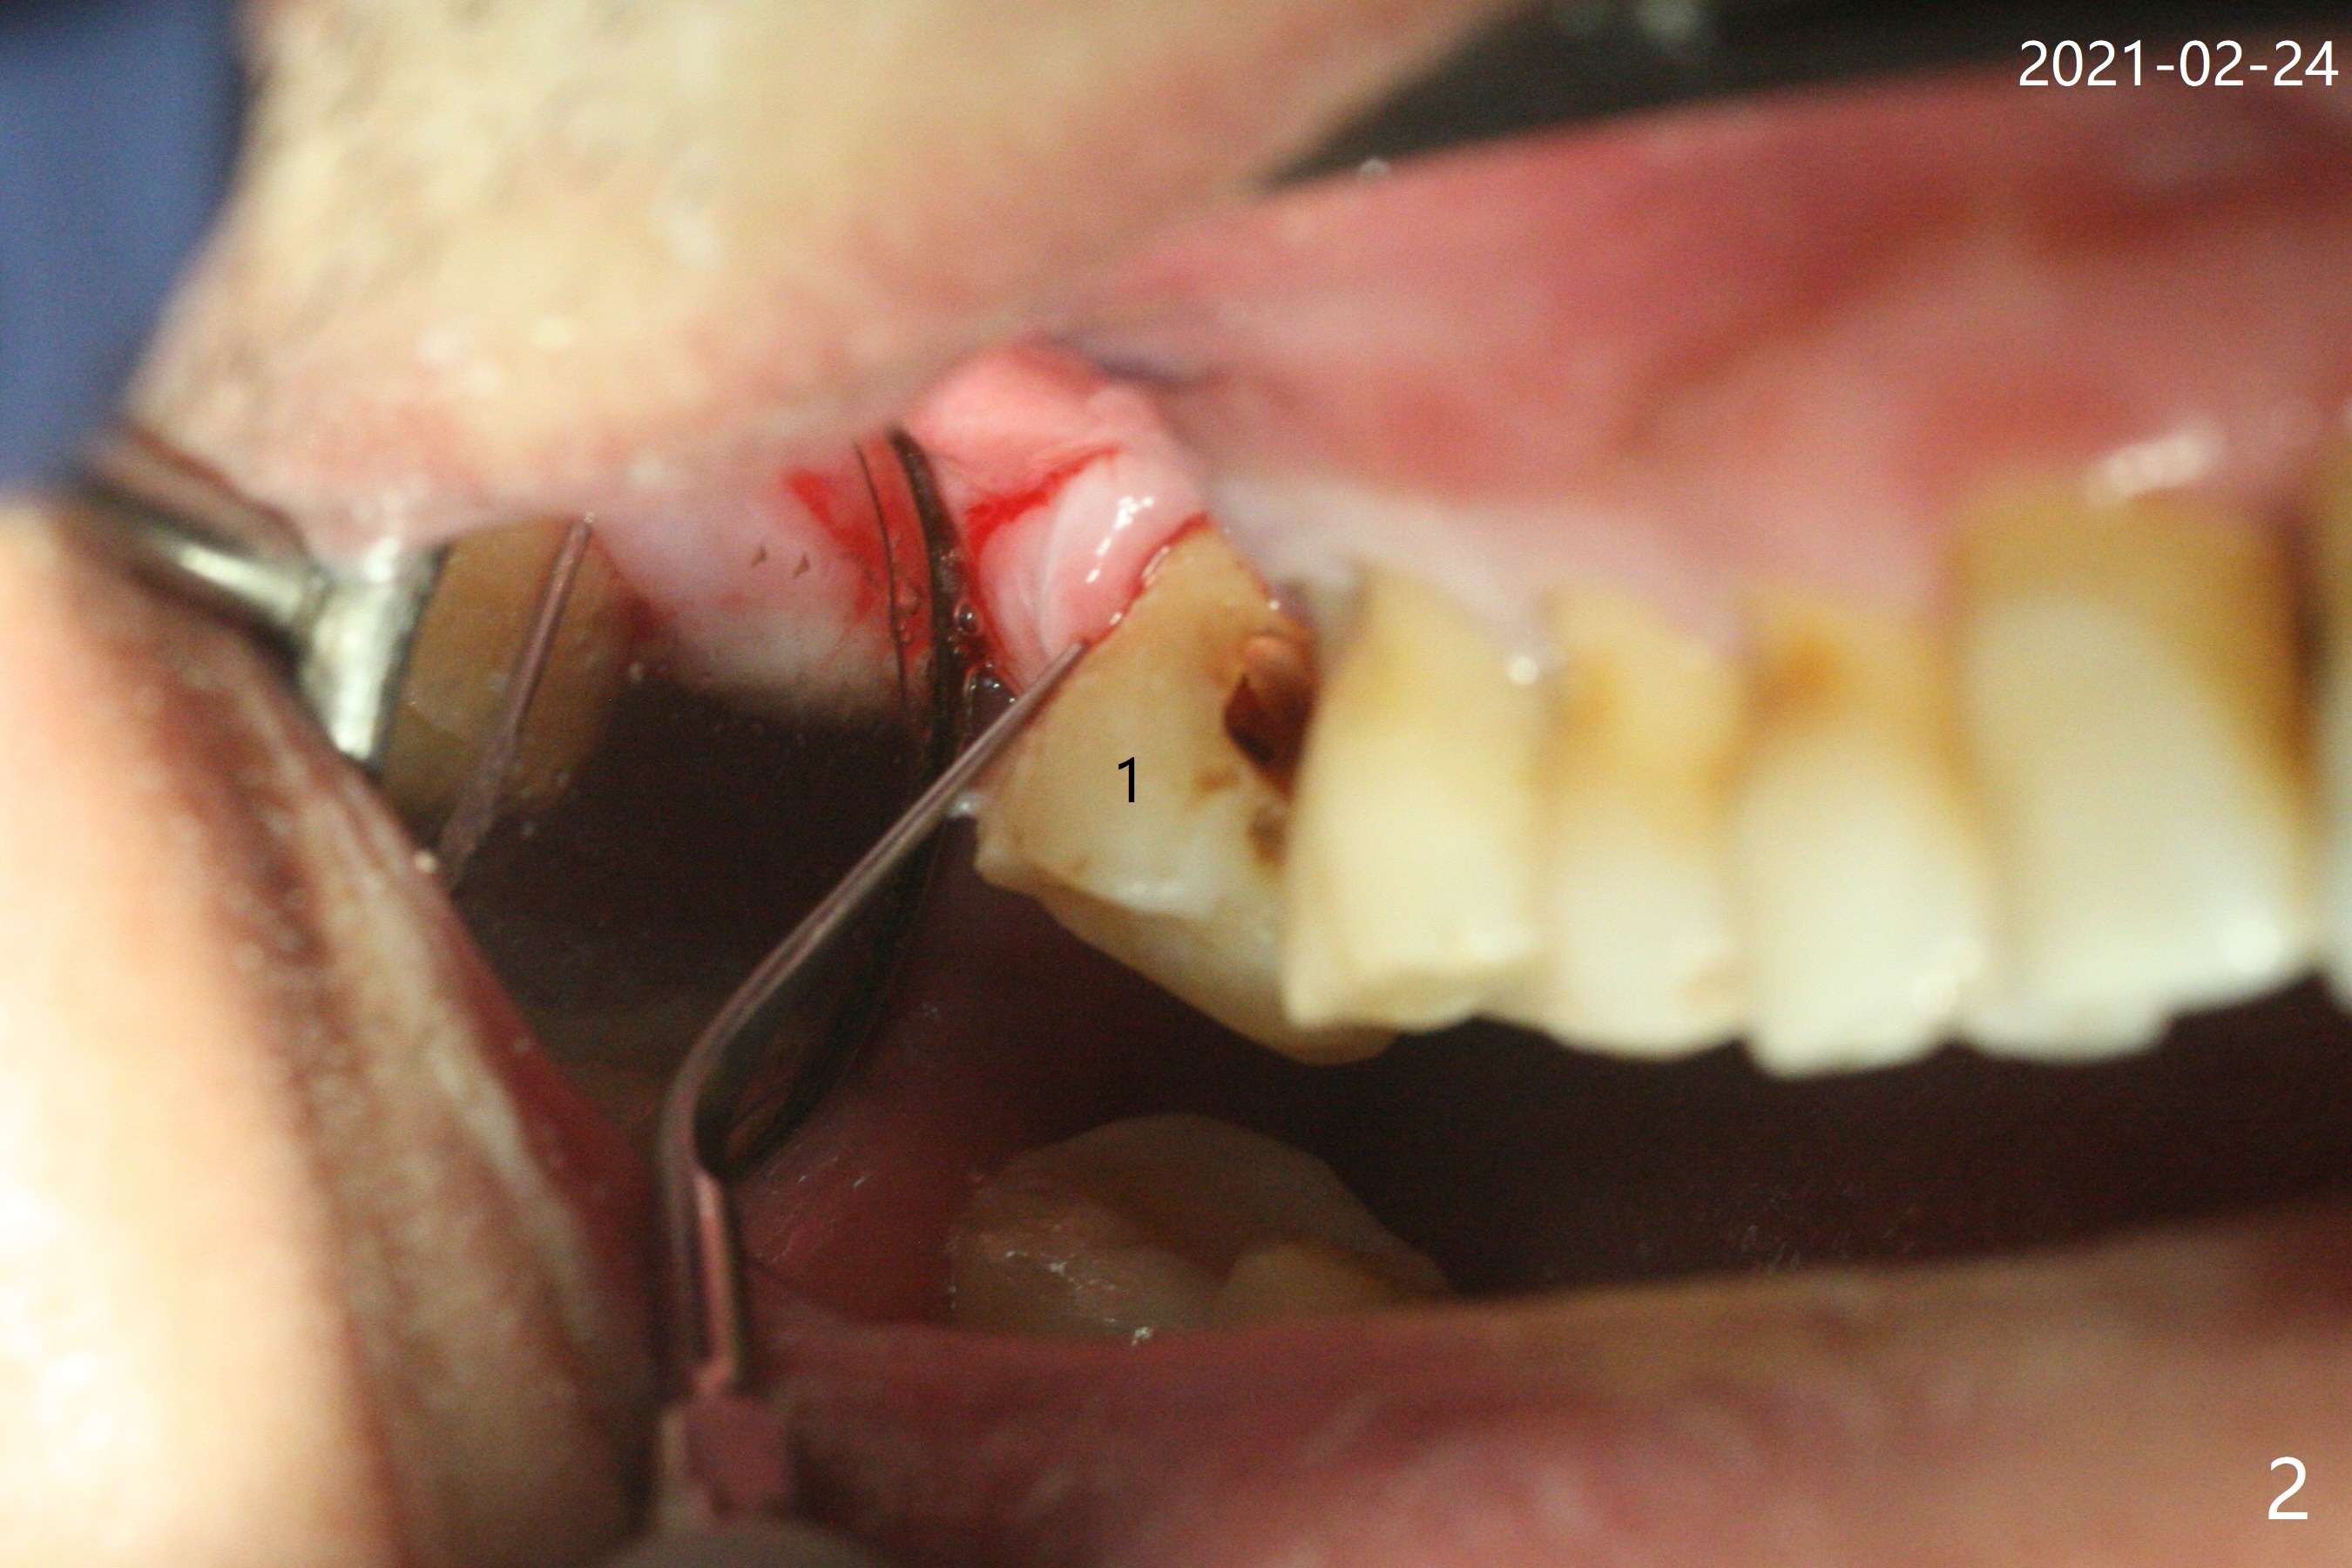

P3作为牙周膜刀

69岁,1号牙无症状(图一),去外州照顾孙子前,准备修补或者拔除,去龋后发现涉及牙髓(死髓),使用P3(图二)试图切断牙周膜,但是发觉不是很利索(图三),有什么窍门?